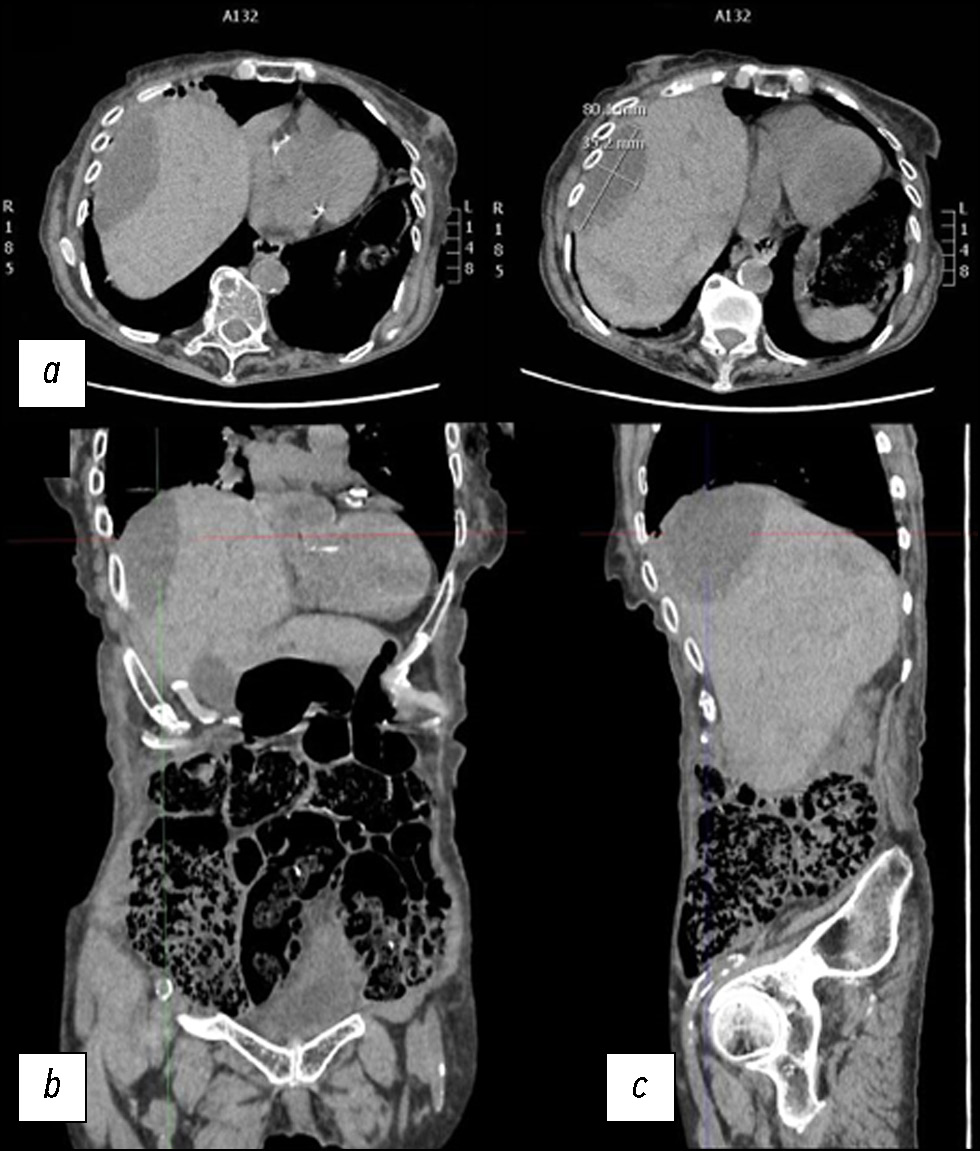

Разрыв паренхимы печени — редкое, но потенциально смертельное состояние, которое может быть вызвано травмой, ятрогенными факторами, спонтанными причинами и так далее. В данной статье описан клинический случай, в котором представлены диагностические и терапевтические меры, применённые в ходе лечения пациентки со спонтанным разрывом паренхимы печени. Пожилая женщина поступила в отделение неотложной помощи с болью в животе диффузного характера. После клинического обследования ей была проведена компьютерная томография. По результатам первой компьютерной томографии не выявили полномасштабного разрыва паренхимы. Из-за неоднозначности данных, указывающих на то, что боль в животе могла быть вызвана почечной или желчной коликой, поставить ранний диагноз было очень проблематично. В паренхиме печени было обнаружено лишь несколько гиподенсных образований овальной формы, наполненных жидкостью повышенной плотности. Однако боль сохранялась в течение нескольких дней, и ввиду ухудшения состояния пациентки были проведены дополнительные рентгенологические исследования, по результатам которых выявили разрыв паренхимы печени. Это потребовало в дальнейшем применения метода артериографии, а также длительного пребывания в стационаре до клинического разрешения.